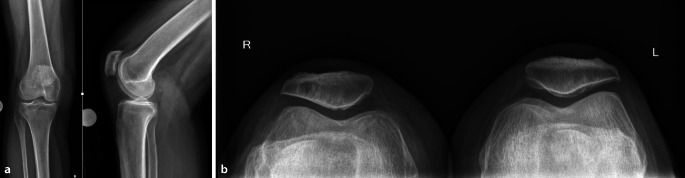

Background: Isolated patellofemoral osteoarthritis is a degenerative disease of the knee joint that may cause disabling pain and functional limitations. When conservative therapy has failed, arthroplasty can significantly improve the quality of life and mobility of affected patients. In such cases, it is important to select the most suitable implant for the patient on an individual basis. This article discusses the decision-making process between patellofemoral arthroplasty, total knee replacement, and bicondylar replacement without patellar resurfacing.

Therapeutic options: Patellofemoral arthroplasty is mainly used in younger patients and, if implanted correctly, can lead to good results and a delay in the need for total knee replacement. In older patients with isolated patellofemoral osteoarthritis, total knee replacement is usually the preferred option due to its predictable good outcomes and a lower revision rate. In selected cases, particularly with severely thinned patella, retropatellar resurfacing should not be done.